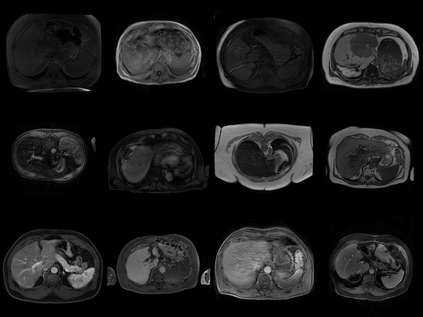

Clinically deployed segmentation models are known to fail on data outside of their training distribution. As these models perform well on most cases, it is imperative to detect out-of-distribution (OOD) images at inference to protect against automation bias. This work applies the Mahalanobis distance post hoc to the bottleneck features of a Swin UNETR model that segments the liver on T1-weighted magnetic resonance imaging. By reducing the dimensions of the bottleneck features with principal component analysis, OOD images were detected with high performance and minimal computational load.